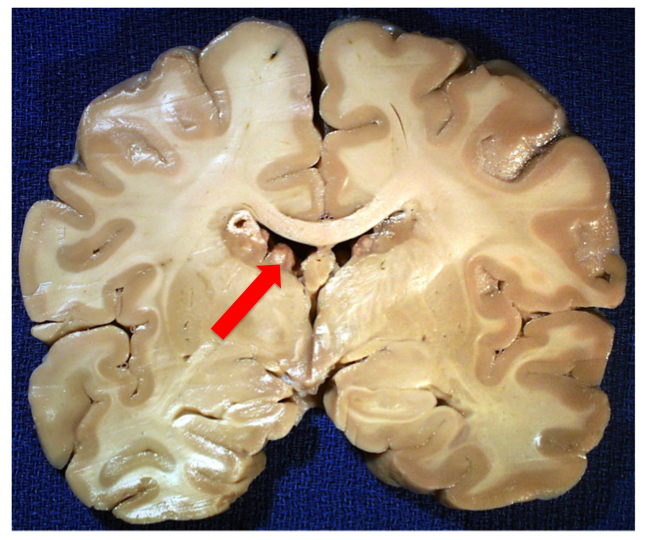

A coronal section of a brain from someone with Tuberous Sclerosis, a syndromic form of autism that is usually a result of a loss-of-function mutation in either the TSC1 or TSC2 genes and which causes upregulation of mTOR pathway activity, leading to increased cell growth and proliferation. In this case, you can easily see the tuberous growths lining the lateral ventricles. Image borrowed from here.

Except in the case of an ongoing neoplasia, the tubers in Tuberous Sclerosis only arise during that GD 40-120 day period. And the same can be said of nonsyndromic autism. And so what do we find in the majority of cases of autistics? We find evidence of hyperplasias in the form of increased minicolumnar numbers, focal dysplasias, and heterotopias, the latter which are neurons which have failed to migrate properly and are located inappropriately in either the gray or white matter [1, 2, 3]. (Because precise timing of proliferation is vital for newborn neurons to receive their proper cues for differentiation and migration, being born at the “wrong time” can lead to miscommunication and the stranding of cells along their developmental and migratory paths.)